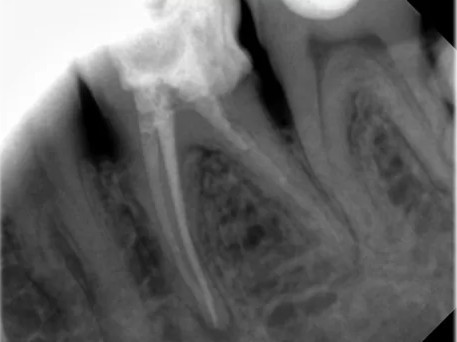

Рентген зубов

Рентген зубов в Санкт-Петербурге